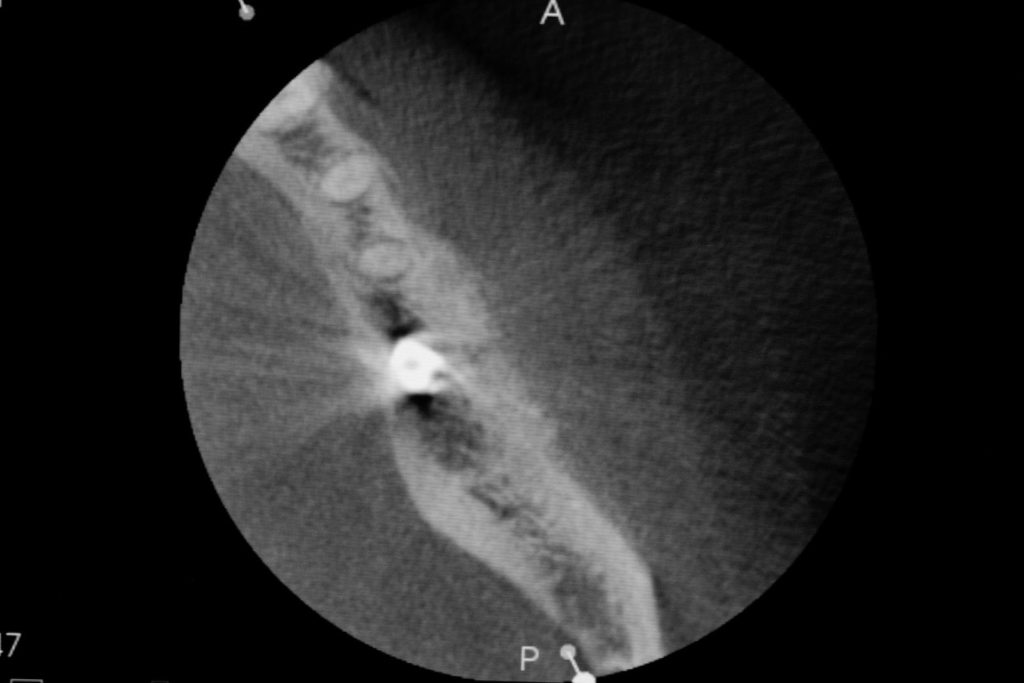

Przed podjęciem leczenia należy określić stopień zaniku kości szczęk oraz żuchwy. W tym celu przeprowadza się badanie kliniczne oraz odpowiednią diagnostykę obrazową pacjenta. Uwzględnia ona zdjęcie panoramiczne OPG jako podstawę dwuwymiarowego obrazowania podłoża kostnego oraz możliwe jest badanie tomograficzne CT lub bardziej precyzyjna tomografia stożkowa CBCT. Opcjonalnie wykorzystywana diagnostycznie tomografia pozwala na bardziej wnikliwą ocenę stopnia zaniku kości w trójwymiarowym, przestrzennym obrazie.

Zatoki szczękowe to symetrycznie umieszczone w kościach szczęk przestrzenie powietrzne, posiadające komunikację z jamą nosa. Średnio pojemność zatok wynosi 24 cm3, a ściany wyścielone są błoną śluzową (membrana Schneidera). Dno zatoki szczękowej stanowi wyrostek zębodołowy, w którym umieszczone są zęby, często zlokalizowane tuż pod cienką wyściółką zatoki. Statystycznie najwęższy obszar kostny w tej strefie zlokalizowany jest na wysokości zębodołów pierwszego i drugiego zęba trzonowego.

• Metoda otwarta – opisana w 1980 przez Jamesa i Boyna – polega na chirurgicznym dostępie do zatoki szczękowej poprzez jej boczną ścianę, następnie delikatnej preparacji, oddzieleniu wyściółki (błony Schneidera) bez jej perforacji, umieszczeniu pomiędzy nią a dnem zatoki materiału odbudowującego kość. Zabieg podniesienia dna zatoki szczękowej może przebiegać z jednoczesnym wszczepieniem implantów lub wszczepieniem ich w czasie odroczonym o 6–8 miesięcy. Warunkiem jednoczesnego wszczepienia implantów jest możliwość pierwotnie stabilnego ich umocowania w pozostałej własnej kości wyrostka zębodołowego. Najmniejsza jej ilość wg niektórych autorów to 1 mm.

• Metoda zamknięta – opisana w 1994 przez Summersa – bez szerokiego otwierania zatoki szczękowej, stosowana w sytuacjach wymagających niewielkiego zakresu rekonstrukcji na wysokość. W tej metodzie materiał regeneracyjny do odbudowy kości wprowadza się przez nawiercony kanał, komunikujący się z zatoką w pozycji zaplanowanej do wszczepienia implantu, lub tylko kondensuje się (zagęszcza, rozpycha i wydłuża) obszar kości dla uzyskania stosownej jej ilości i gęstości dla stabilnego umocowania implantu. Zabieg odbudowy kostnej wg Summersa wykonuje się przy użyciu specjalnego instrumentarium – zestawu osteotomów. Uzyskuje się dodatkowo 2–4 mm kości na wysokość